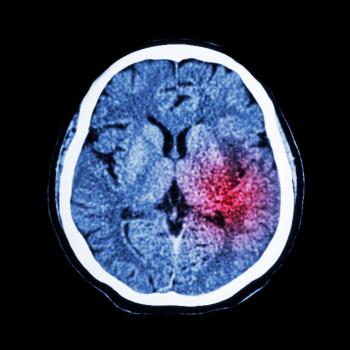

缺血性中风是最常见的形式,约占所有中风的87%。它在含氧丰富的动脉血流向大脑受阻时发生,主要是由于血凝块堵塞。

出血性中风约占所有中风的13%,是因为脑血管渗漏或破裂引起的。

中风究竟会对人造成怎样的影响取决于中风发生在大脑中的哪一个侧面以及它造成损伤的量。比如,有些人可能会出现暂时性的手臂或腿部无力,而其他人可能会失去说话或走路的能力。